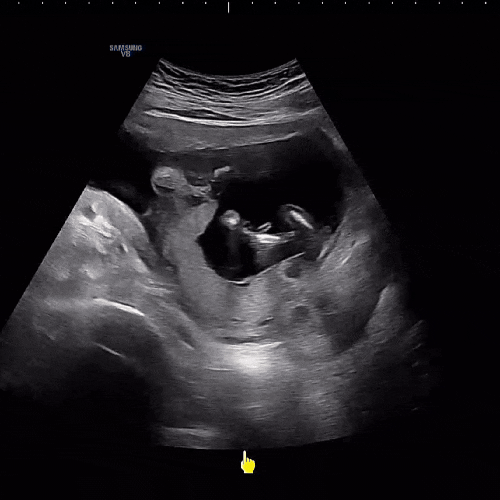

? 완두 14~16주+ 일상 / 2차 기형아 검사 / 성별확정 / 입덧 안녕 / 리안드림콧 / 베이비빌리

시간이 정말 무섭게 지나가는 요즘 연휴 시작을 맞이해 올려보는 완두와의 일상 #임신14주 #오랑발리 #부림...